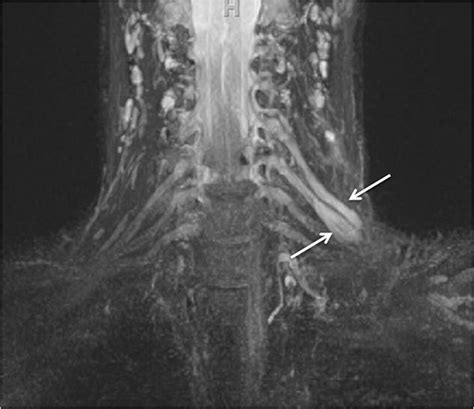

• Brachial Plexus Injuries: Evaluating trauma or inflammatory conditions affecting the network of nerves that control the shoulder, arm, and hand.

To overcome this, this specialized imaging employs specific pulse sequences designed to suppress the signal from fat—which often obscures nerve detail—while enhancing the signal from water-rich tissues like nerves. This process effectively makes the nerves "light up" on the resulting images, allowing radiologists to assess their anatomy, signal intensity, and trajectory in high detail.

Once the images are acquired, they are analyzed by a radiologist with specialized expertise in musculoskeletal or neuroradiology. The goal is to identify changes in the nerve's appearance. For instance, a healthy nerve typically appears as a thin, uniform structure with a consistent signal. In contrast, an injured or compressed nerve may exhibit:

• Increased signal intensity: Often indicative of edema (swelling) or inflammation within the nerve.

• Nerve enlargement (fascicular thickening): A sign that the nerve is being subjected to chronic pressure or trauma.